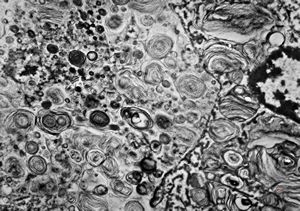

M, 1y. | gangliosidosis - liver